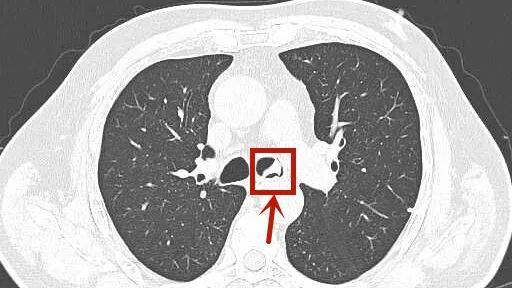

这些不对劲 , 让子女们都担心不已 , 赶紧把周大伯送到了杭州市第三人民医院呼吸内科 。 接诊的丁凌医生询问后 , 怀疑周大伯的气管内存在异物 , 第一时间安排他做胸部CT检查 。 而结果显示气管内有高密度影 , 高度异物可能!

呼吸科主任冷报浪仔细阅片 , 立即联系内镜中心 , 紧急为周大伯安排纤维支气管镜检查:气管镜经声门进入 , 果然发现一异物横跨在气管分叉与左主支气管交界处 。

再仔细一瞧 , 它质硬 , 带小钩 , 大小约3*2*1cm , 这不正是周大伯消失的部分假牙么?